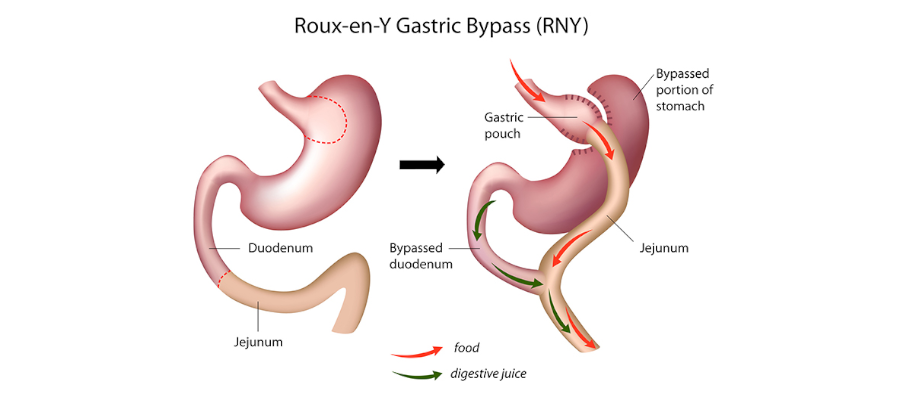

Diese Operation ist eine der ältesten Operationen der Adipositas- und Stoffwechselchirurgie. Sie zählt seit langem als Goldstandart in der Adipositaschirurgie. Im Unterschied zu einer Schlauchmagenoperation wird der Magen nicht entfernt und ein Teil des Darms wird deaktiviert. Es ist eine, sowohl restriktive als auch malabsorptive, bariatrische Operation.

Technik: Diese Operation kann unter Vollnarkose, laparoskopisch oder robotisch durchgeführt werden. Zunächst wird der Magen in 2 Teile geteilt und ein 15-30 ml Magenbeutel wird belassen, die mit der Speiseröhre verbunden ist. Der verbleibende Teil des Magens bleibt funktionsgestört. Der Dünndarm wird 75 cm voraus abgetrennt und das untere Ende wird an den Magen genäht. Das obere Ende wird 100-150 cm vom unteren Ende entfernt genäht. So gelangt die aufgenommene Nahrung zunächst in den gebildeten Dünnmagen und dann in den Dünndarm, der von dort durchtrennt wird. Verdauungsenzyme zu Nahrung befinden sich 100-150 cm voraus. Diese Situation führt zu Malabsorption.